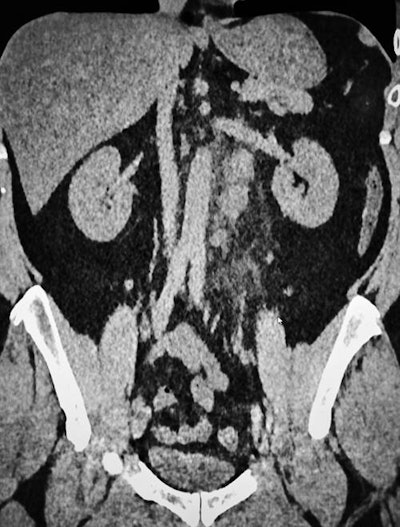

Thanks to the national and international publications and information campaigns, we have become quite aware of the COVID-19 CT features, but soon we had quite a lot of nontypical cases, including patients with extrathoracic findings or severe cases in young people. We have also had some patients from our hemodialysis center presenting with less severe cases and many patients with ear, nose, and throat symptoms or associated diseases, including pulmonary emboli. This is quite a problem in COVID-19 cases that require cooperation with clinicians, especially emergency specialists.